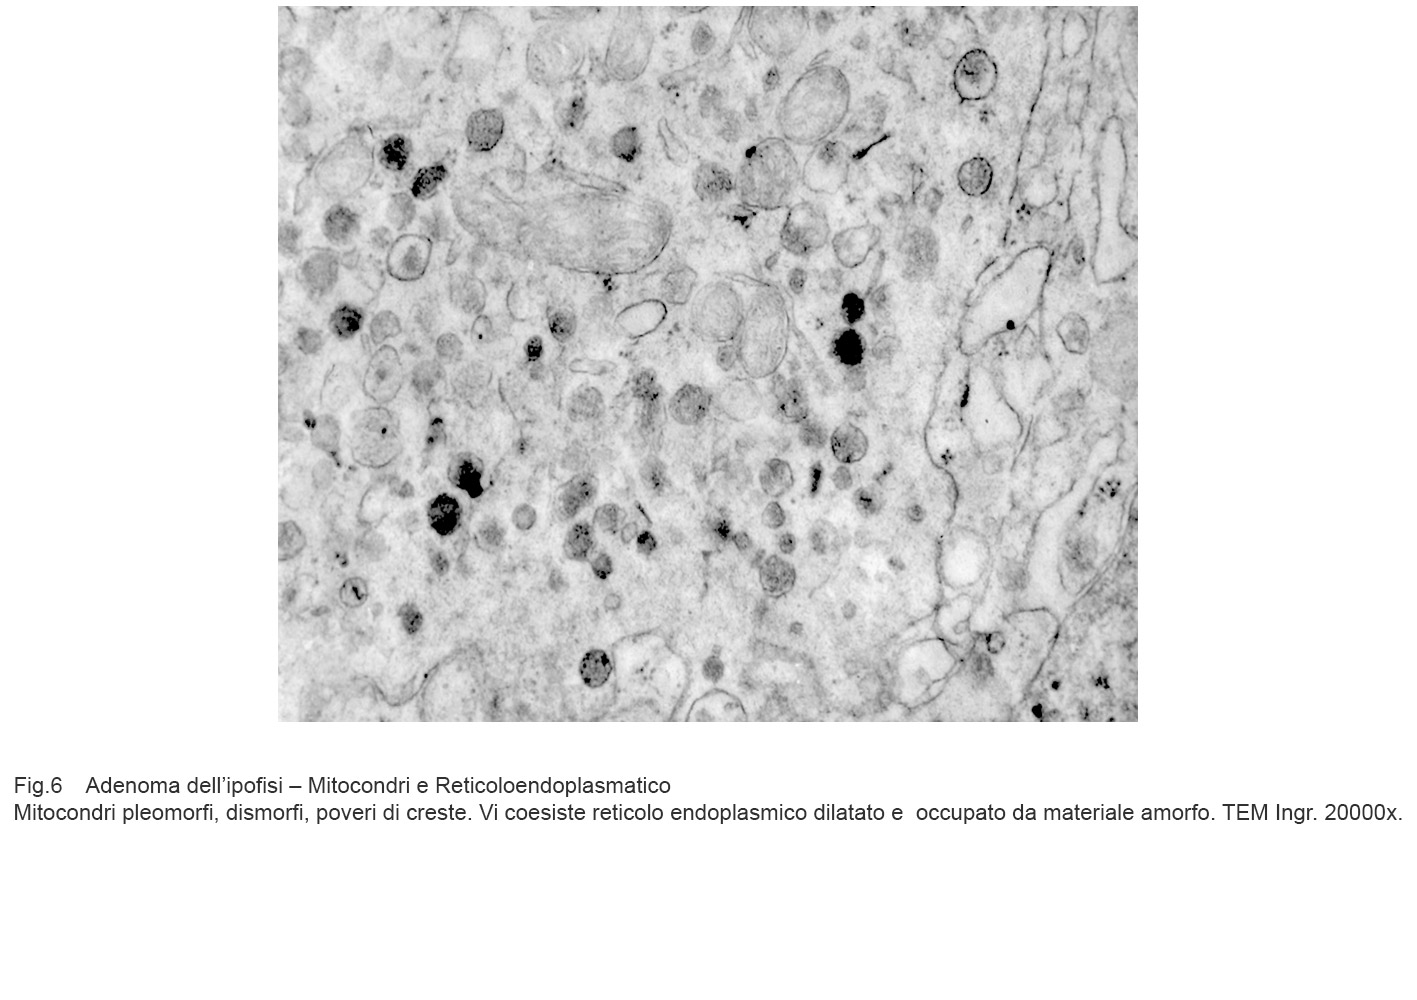

I dati rilevati possono essere sintetizzati nei seguenti punti descrittivi:

Mitocondri e R.E.: mitocondri con microvacuoli e depauperati di creste sono commisti a dilatazione micro-macrovacuolare del reticolo endoplasmico; alcuni di questi vacuoli sono occupati in modo parziale da materiale amorfo.

Fig.5  Fig.6

Fig.6